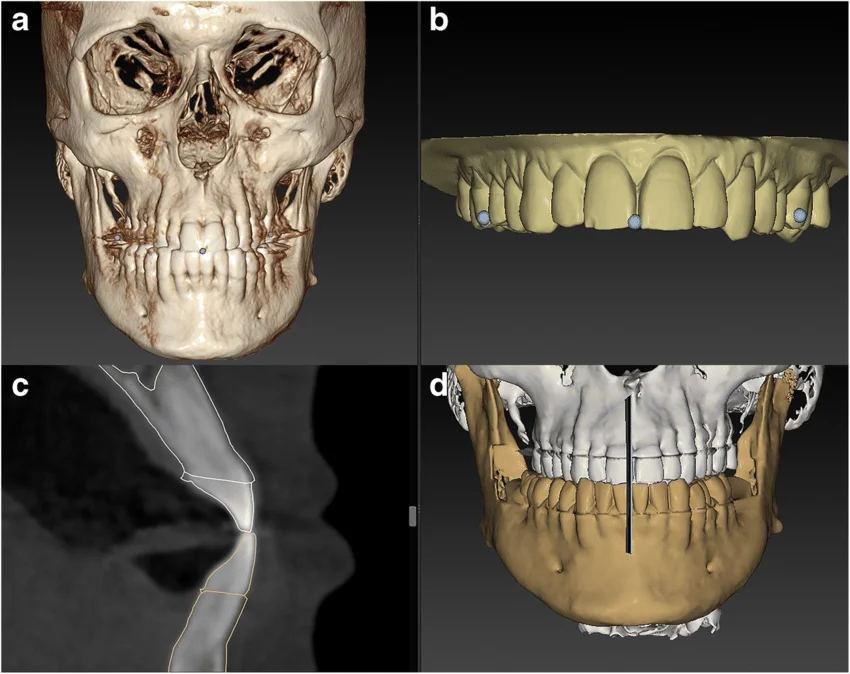

CBCT Scan

View attachment 4444394